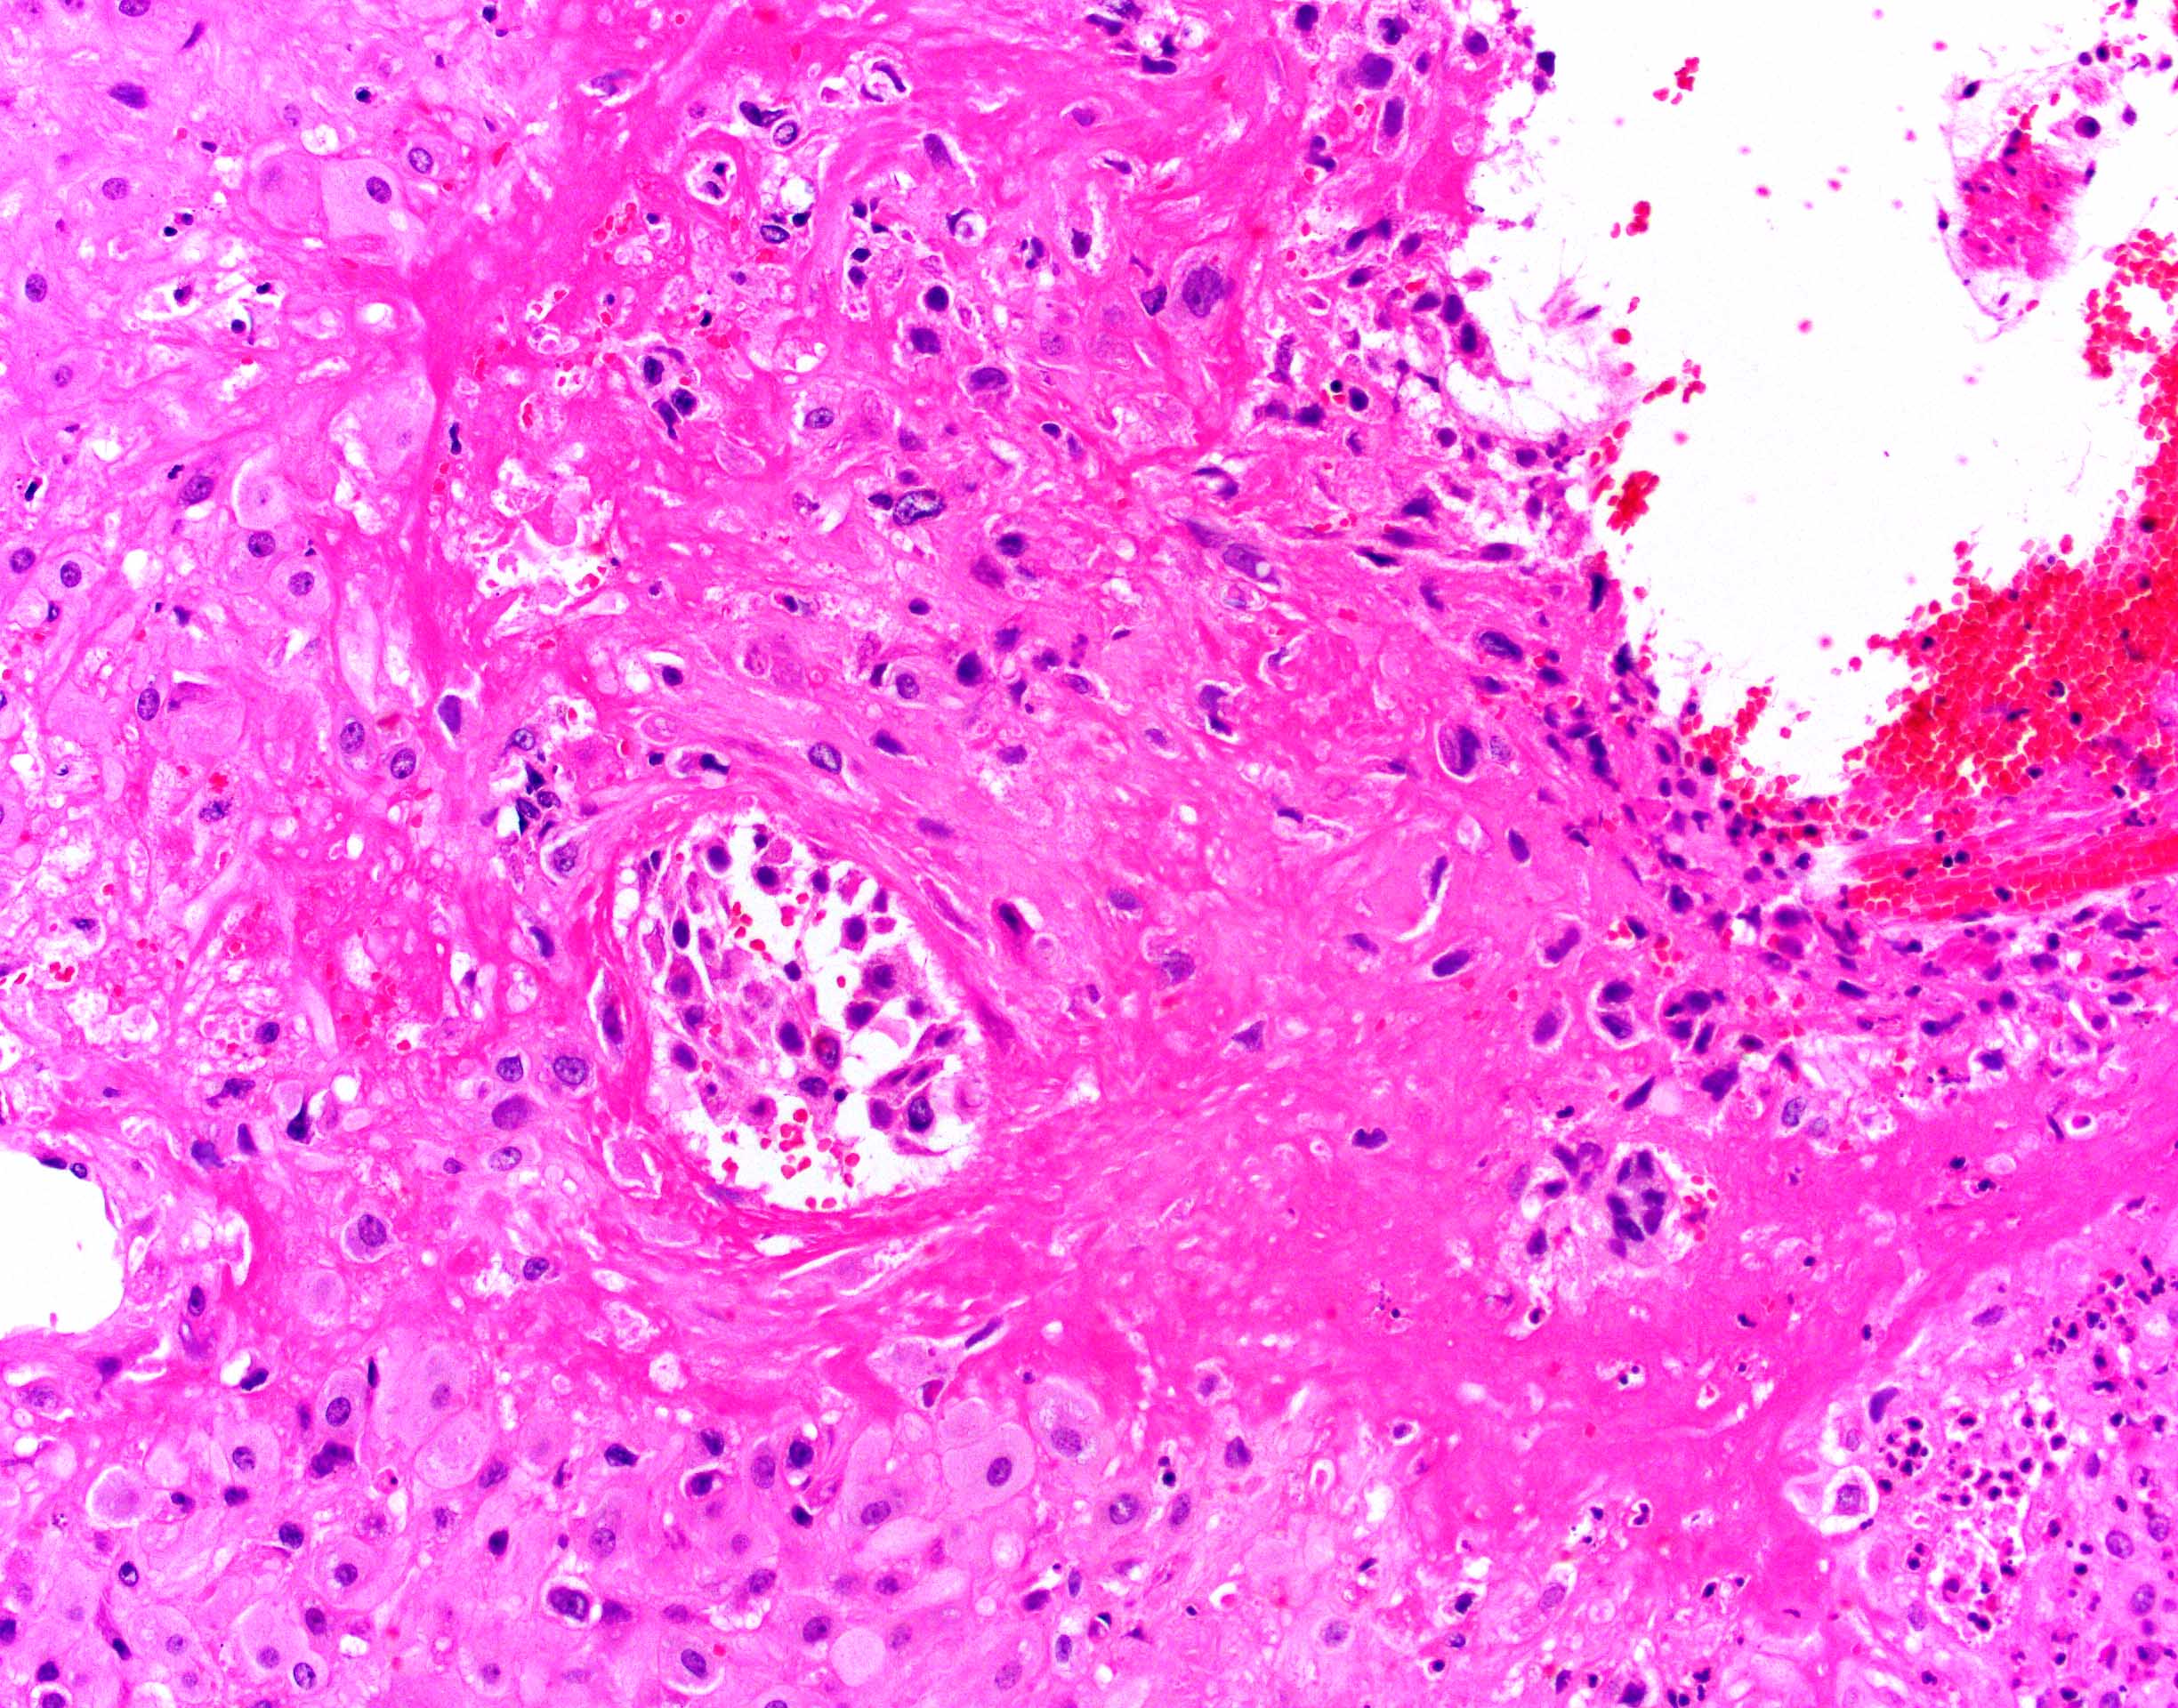

- Gestational / decidualized endometrium:

- Not uncommon to see inflammatory cells, especially lymphocytes but not plasma cells (plasma cells are pathologic)

- Variable amount of decidual necrosis with inflammatory debris

- Placental implantation site:

- Extravillous trophoblast (EVT) within decidualized endometrium, visible maternal vascular remodeling, fibrinoid material in decidua, EVT within vascular wall or within vessel lumens

- Confirms intrauterine pregnancy even in the absence of chorionic villi

- Be careful with interpreting rare villi or syncytiotrophoblast in the absence of implantation site as this could indicate, although rarely, villous migration from a tubal pregnancy

- Other recognizable pathologies (intervillous / maternal space should be empty; if material is present, rule out these pathologies) (Hum Reprod 2007;22:313):

- Chronic histiocytic intervillositis (Malays J Pathol 2020;42:439)

- Massive perivillous fibrin deposition (look for extravillous trophoblast proliferation; otherwise, increased fibrin may be seen with embryonic demise secondary to prolonged retention in utero or secondary to medical abortions)

- Infectious etiologies: marked chronic lymphoplasmacytic or acute inflammation within the maternal vascular space or causing villitis (septic abortions - a critical value)

Microscopic (histologic) images

Contributed by Chrystalle Katte Carreon, M.D. and Drucilla J. Roberts, M.D.